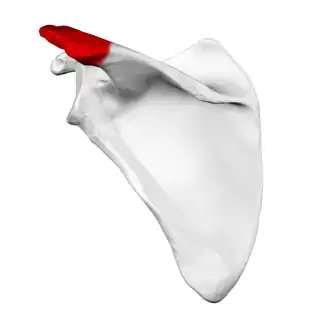

Left scapula, posterior view. Acromion shown in red. | |

Left scapula. Acromion shown in red.

Left scapula. Acromion shown in red. -